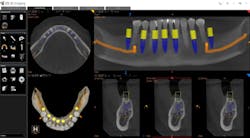

Whether it is an implant consultation for a single implant (figure 4), multiple implants, or full-mouth reconstruction, advanced 3-D software, such as the CS 3D Imaging software, offers you the ability to virtually plan the implant placement in regard to bone height, width, and density with respect to anatomical structures. Once planned, this information is reviewed with the patient in a clear and concise way that is easily understood (figure 5). In my experience, patients often state that they didn’t know that this type of technology was even possible within a dental office. Because of these reasons and more, I have found that case acceptance has gone up exponentially.

Figure 5: Virtual planning of immediate implant placement

In today’s practice, dental professionals should have imaging that can satisfy all their diagnostic needs. CBCT is an investment that generates a strong return, especially when it covers nearly every routine situation as well as more advanced clinical situations (figure 6). With the systems currently available, you can cost-effectively take the essential first step with 2-D panoramic views and investigate in depth with powerful 3-D imaging. As a result, you can offer and perform more procedures in your practice, improving the overall level of patient care.

Figure 6: A full-mouth implant reconstruction achieved with CBCT